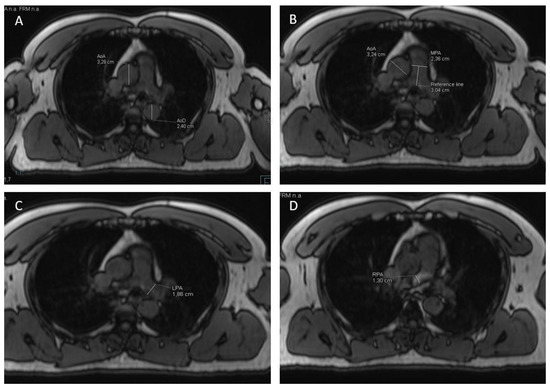

2.3. MR-Image Analysis for Measurement of Vessel Diameters